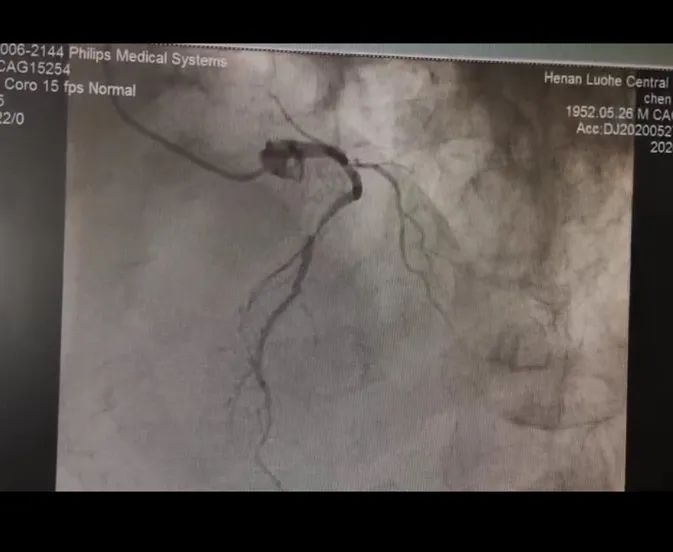

患者陈大爷今年78岁,身患多种高危疾病,近一年来反复心绞痛发作,至当地医院诊断为“冠状动脉粥样硬化性心脏病”,后多次发作,口服药物后病情仍未得到缓解,为求进一步治疗,经人介绍来到漯河市中心医院,经心内科进行冠脉造影检查显示为“左主干+三支血管病变”。

造影显示左主干+三支血管病变